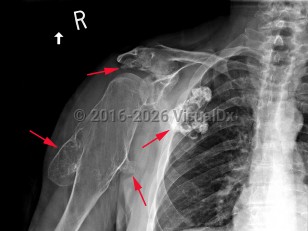

A rare, autosomal dominant genetic condition resulting in the development of multiple osteochondromas (exostoses) at the metaphyses or diaphyses of long bones, commonly affecting the vertebrae, ribs, limbs, hands, fingers, shoulders, and hips. Caused by mutations in the EXT1 or EXT2 genes. Osteochondromas are benign tumors consisting of bone overgrowths and capped with cartilage. They begin formation during regular bone growth and stop growing when the patient reaches skeletal maturity. The severity of the condition is widely variable. The presence of osteochondromas can cause pain, short stature, various deformities, limb length discrepancy, hip dysplasia, and movement difficulties. The deformities may also cause nerve, blood vessel, or spinal cord compression. Most exostoses remain benign, but some may become malignant.